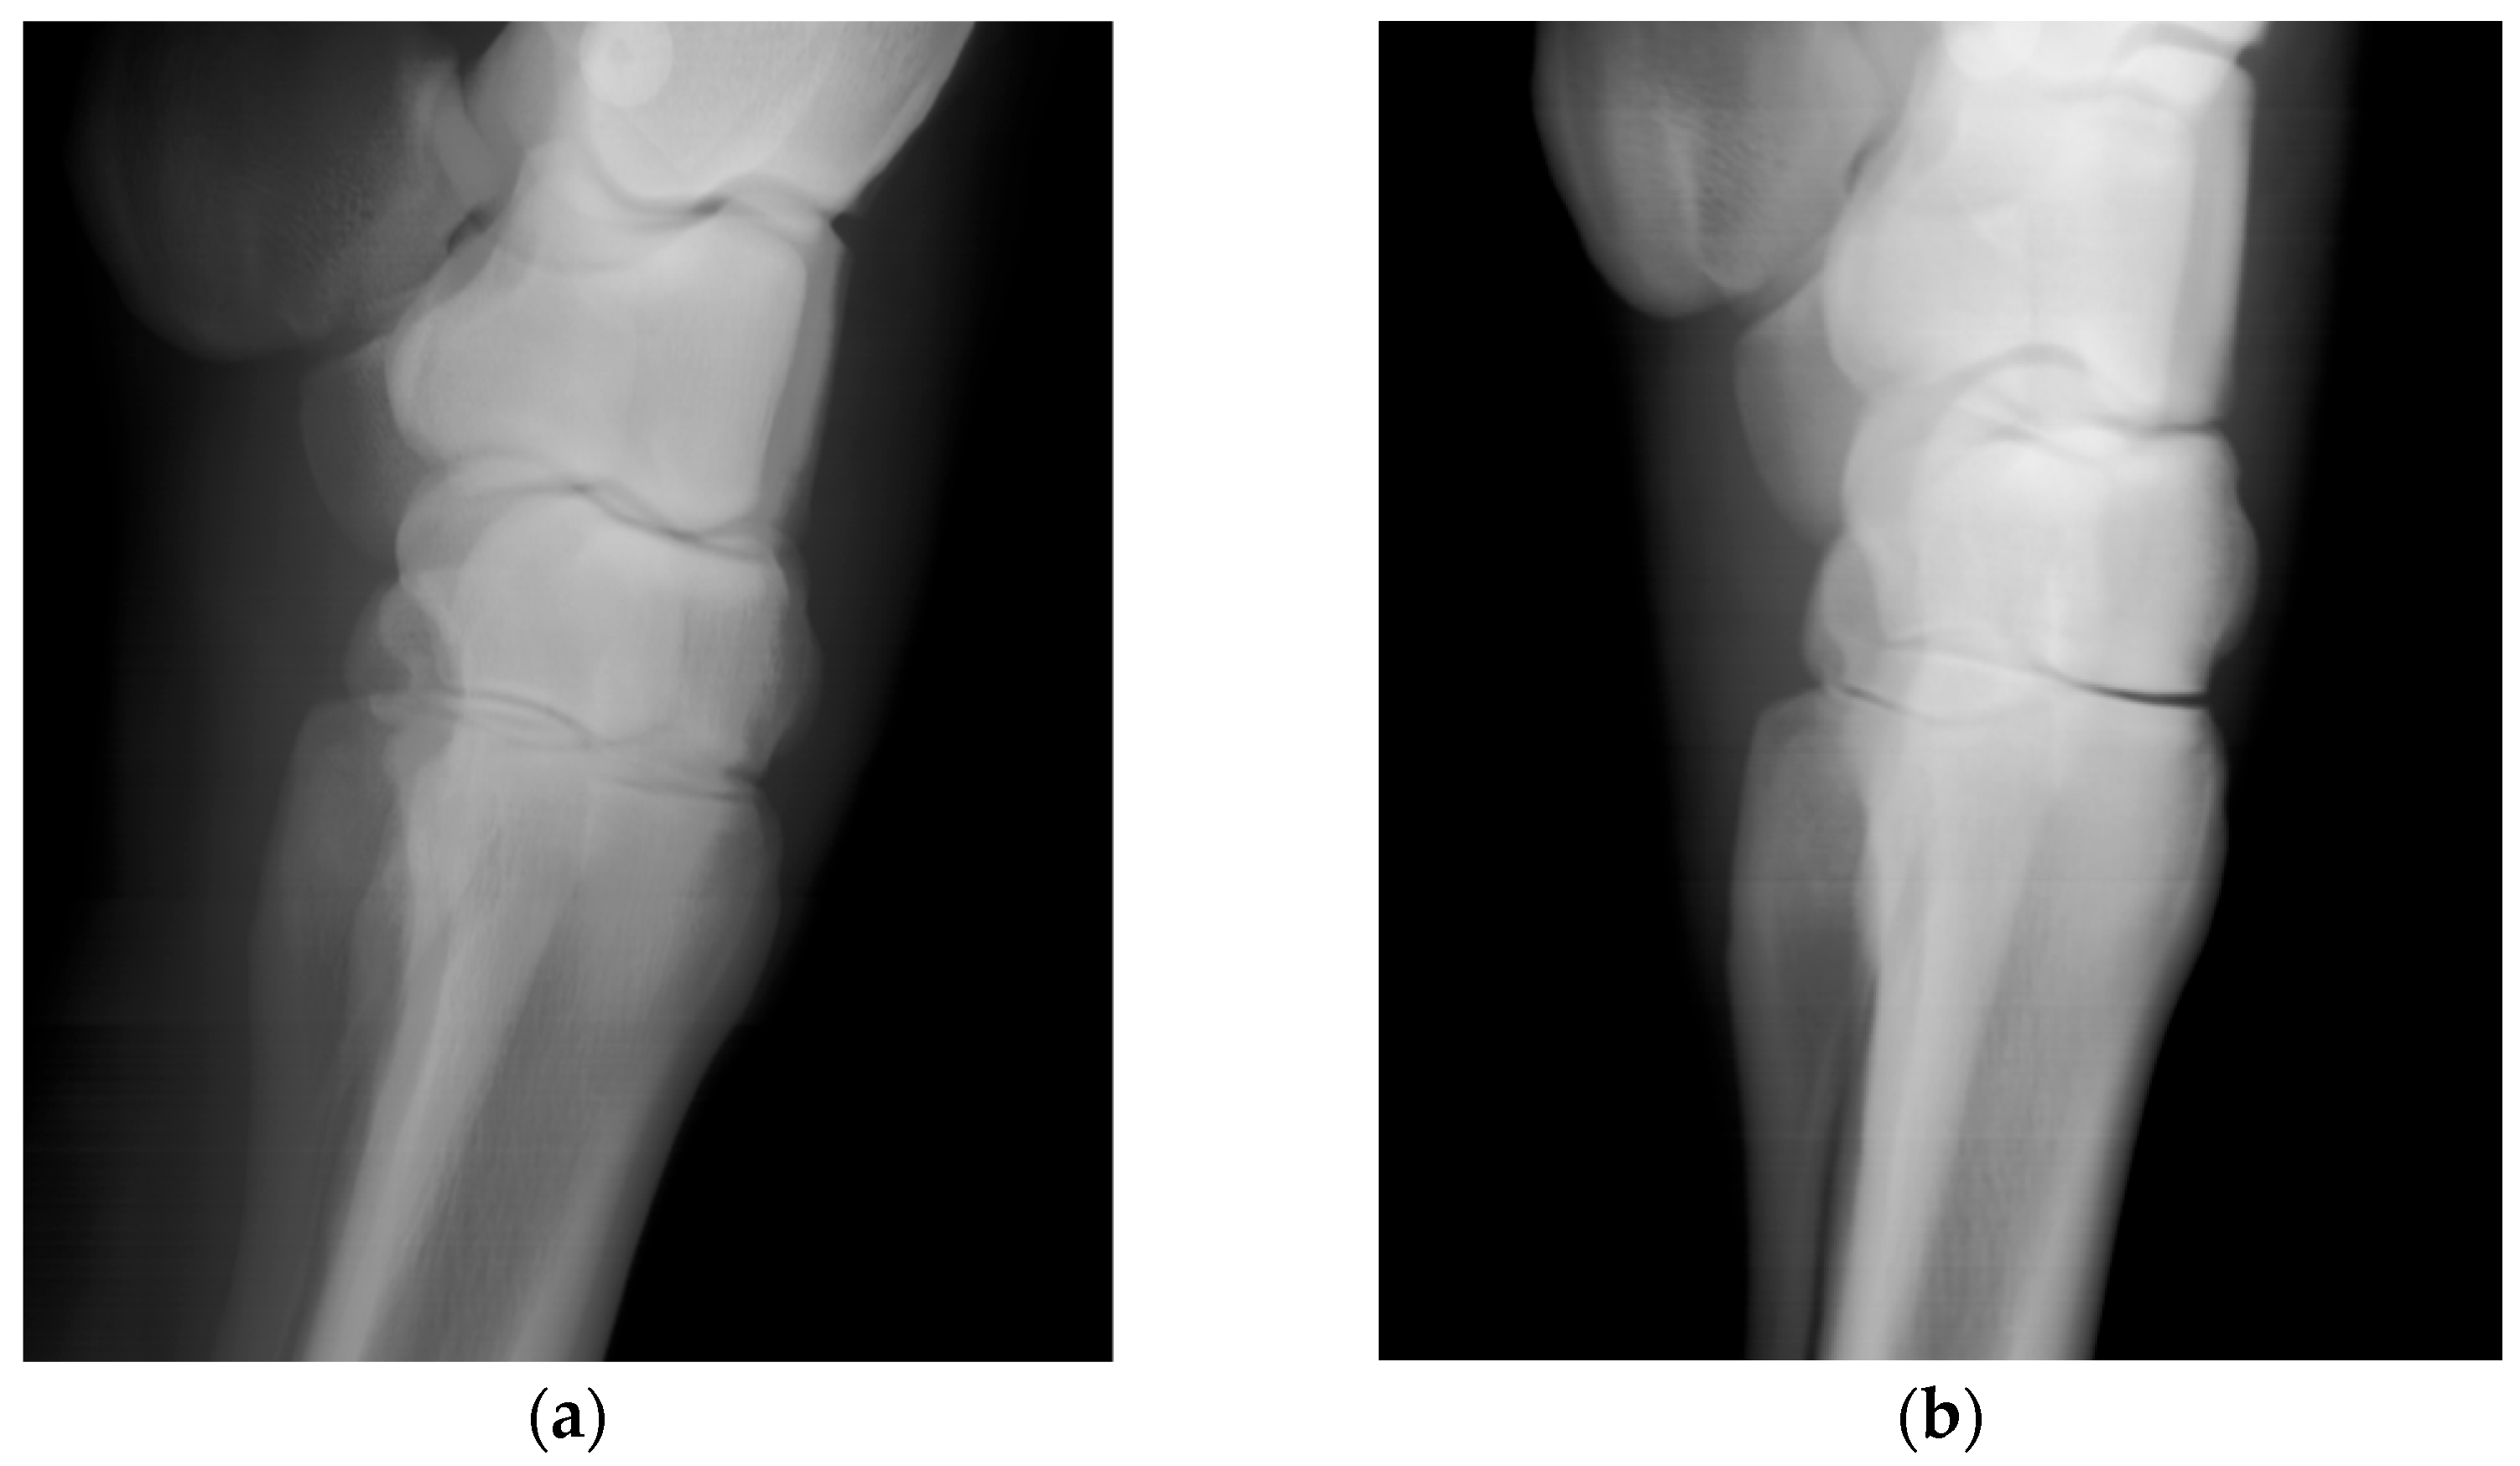

Scans of the horses’ distal forelimb, focusing on the hock and metatarsal, were performed utilizing the calibrated DH parameters. The images are clear and permit visualization of bone trabecular-level detail (Figure 5). For comparison, the second prismatic joint on the detector side’s θ parameter was returned to its initial value and an image of an equine lumbar segment phantom was collected (Figure 6). There is an obvious improvement in image sharpness with the calibrated system (Figure 6).

A two-level optimization scheme was adequate to converge DH mechanism parameters (outer loop) and the offset of the robotic system coordinate system from the motion capture system (inner loop). Perturbations of DH parameters from initial guesses to converged values were typically a few millimeters or degrees, except for several rotations, where the calibrated reference value is arbitrary. The offsets transforming the camera coordinate system to the base of the robot changed by upwards of 100 mm, as it was dependent upon the arbitrary positioning of the motion capture “L-frame” when the camera system was calibrated. The final errors for the optimized mechanism model showed standard deviations in the position error of approximately one millimeter, consistent with the measurement uncertainties of the motion capture system. The orientation error improved, but the initial average error was not very large. This makes sense, since the initial joint angles were the best manual measurement possible given the physical system. Figure 6 shows that mechanism parameter optimization is necessary to produce diagnostic images with this system.

Figure 6. Images showing improvements of imaging performance due to DH parameter optimization. For images (a,b) a single parameter, the θ value for the detector’s second prismatic joint, was kept at its initial value. Images (c,d) used the full set of optimized parameters. Images (b,d) are contrast-adjusted, zoomed in, and leveled to view the bony features of the lumbar segment phantom.